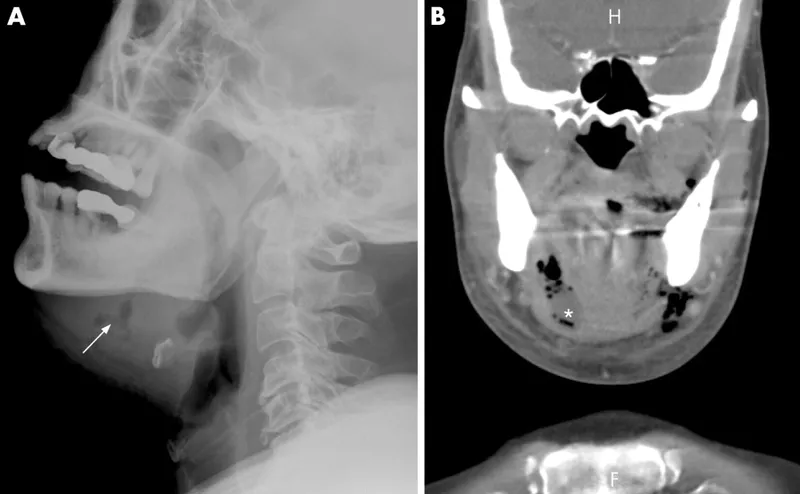

- Ludwig's Angina: Submandibular/sublingual cellulitis; airway risk.

⭐ Ludwig's Angina: Aggressive, rapidly spreading cellulitis of the floor of the mouth (sublingual, submylohyoid, submandibular spaces); often odontogenic. Airway compromise is a major concern. Critical to secure airway early!